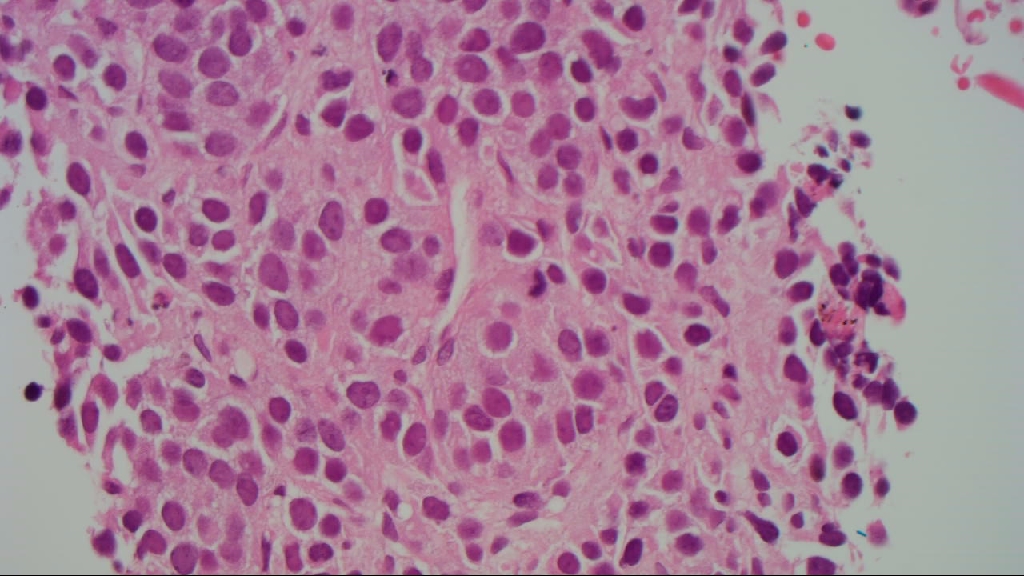

1.   Dissociated fragments of tumour with mild pleomorphism, round to oval nuclei and nucleoli are not easily seen.  There are occasional mitotic figures and focal punctate necrosis but there is insufficient material for a formal mitotic count/grading.

2.   Scanty fragments of cohesive tumour cells with a packeted architecture and minimal nuclear pleomorphism.  A single mitotic figure is identified but there is insufficient material for a formal mitotic count.  The tumour cells are immunopositive for MNF116 (with paranuclear accentuation), diffuse nuclear TTF 1, chromogranin, and the MIB-1 proliferation index is 16%.

1-3.  EBUS samples - neuroendocrine tumour in specimens 1 and 2 (see text).

Comment: Please correlate with the clinical impression.  Sampling is insufficient for formal grading but the clinical distribution of tumour and the presence of punctate necrosis and mitotic figures aludes to at least atypical carcinoid tumour.

insular/packeted architecture